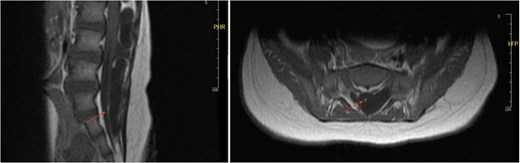

An 11-month-old female infant, born to unrelated Saudi parents, was referred to our facility with unilateral left coronal craniosynostosis, congenital microcephaly, global developmental delay, and a confirmed ZIC1 gene mutation. Comorbidities included a patent foramen ovale, aortopulmonary collateral vessel, G6PD deficiency, and gastroesophageal reflux disease (GERD). At birth head circumference was 29 cm (<first percentile), and progressive skull asymmetry and squinting were noted over time. Developmentally, she exhibited delayed gross and fine motor skills with limited object transfer. On examination, she was alert and visually tracking, with inward ocular deviation (esotropia). Head circumference was 37 cm (<first percentile) with anterior plagiocephaly and towering of the left frontal region (Fig. 1). Pupils were equal and reactive. Fundoscopy and cranial nerve examinations were unremarkable. Gross motor power was within normal limits, except for moderate lower limb spasticity. 3D reconstruction computed tomography (CT) confirmed premature fusion of the left coronal suture with subtle elevation of the superolateral orbital rim, indicating harlequin sign (Fig. 1). Brain CT showed corpus callosum agenesis, colpocephaly, mild ventriculomegaly, right cerebellar and pontine hypoplasia, and a large cisterna magna, consistent with the reported ZIC1-related malformation spectrum (Fig. 2). Given the progressive deformity and concerns of increased intracranial pressure that might be partially contributing to her neurodevelopmental delay, anterior cranial vault expansion with fronto-orbital advancement was performed jointly by the neurosurgery and plastic craniofacial teams (Fig. 3). Intraoperatively, left-sided dural tension was appreciated, indicating localized increased intracranial pressure. The orbital bandeau was reshaped and advanced, achieving immediate cosmetic improvement (Fig. 4). The patient tolerated the surgery well and recovered uneventfully. At her 4-month follow-up, she showed developmental progress including standing without support, purposeful hand use, and verbalization (“Baba”). At 6-month follow-up, brain CT revealed areas of bone resorption which led to the placement of a ventriculo-peritoneal shunt (Fig. 5). The known association of ZIC1 mutation with tethering of the cord prompted spinal magnetic resonance imaging (MRI) screening. Positive findings indicated an untethering procedure, which was successfully done (Fig. 6).

Axial and sagittal views of spinal MRI showing tethering of the cord at the level of S1 (arrows).